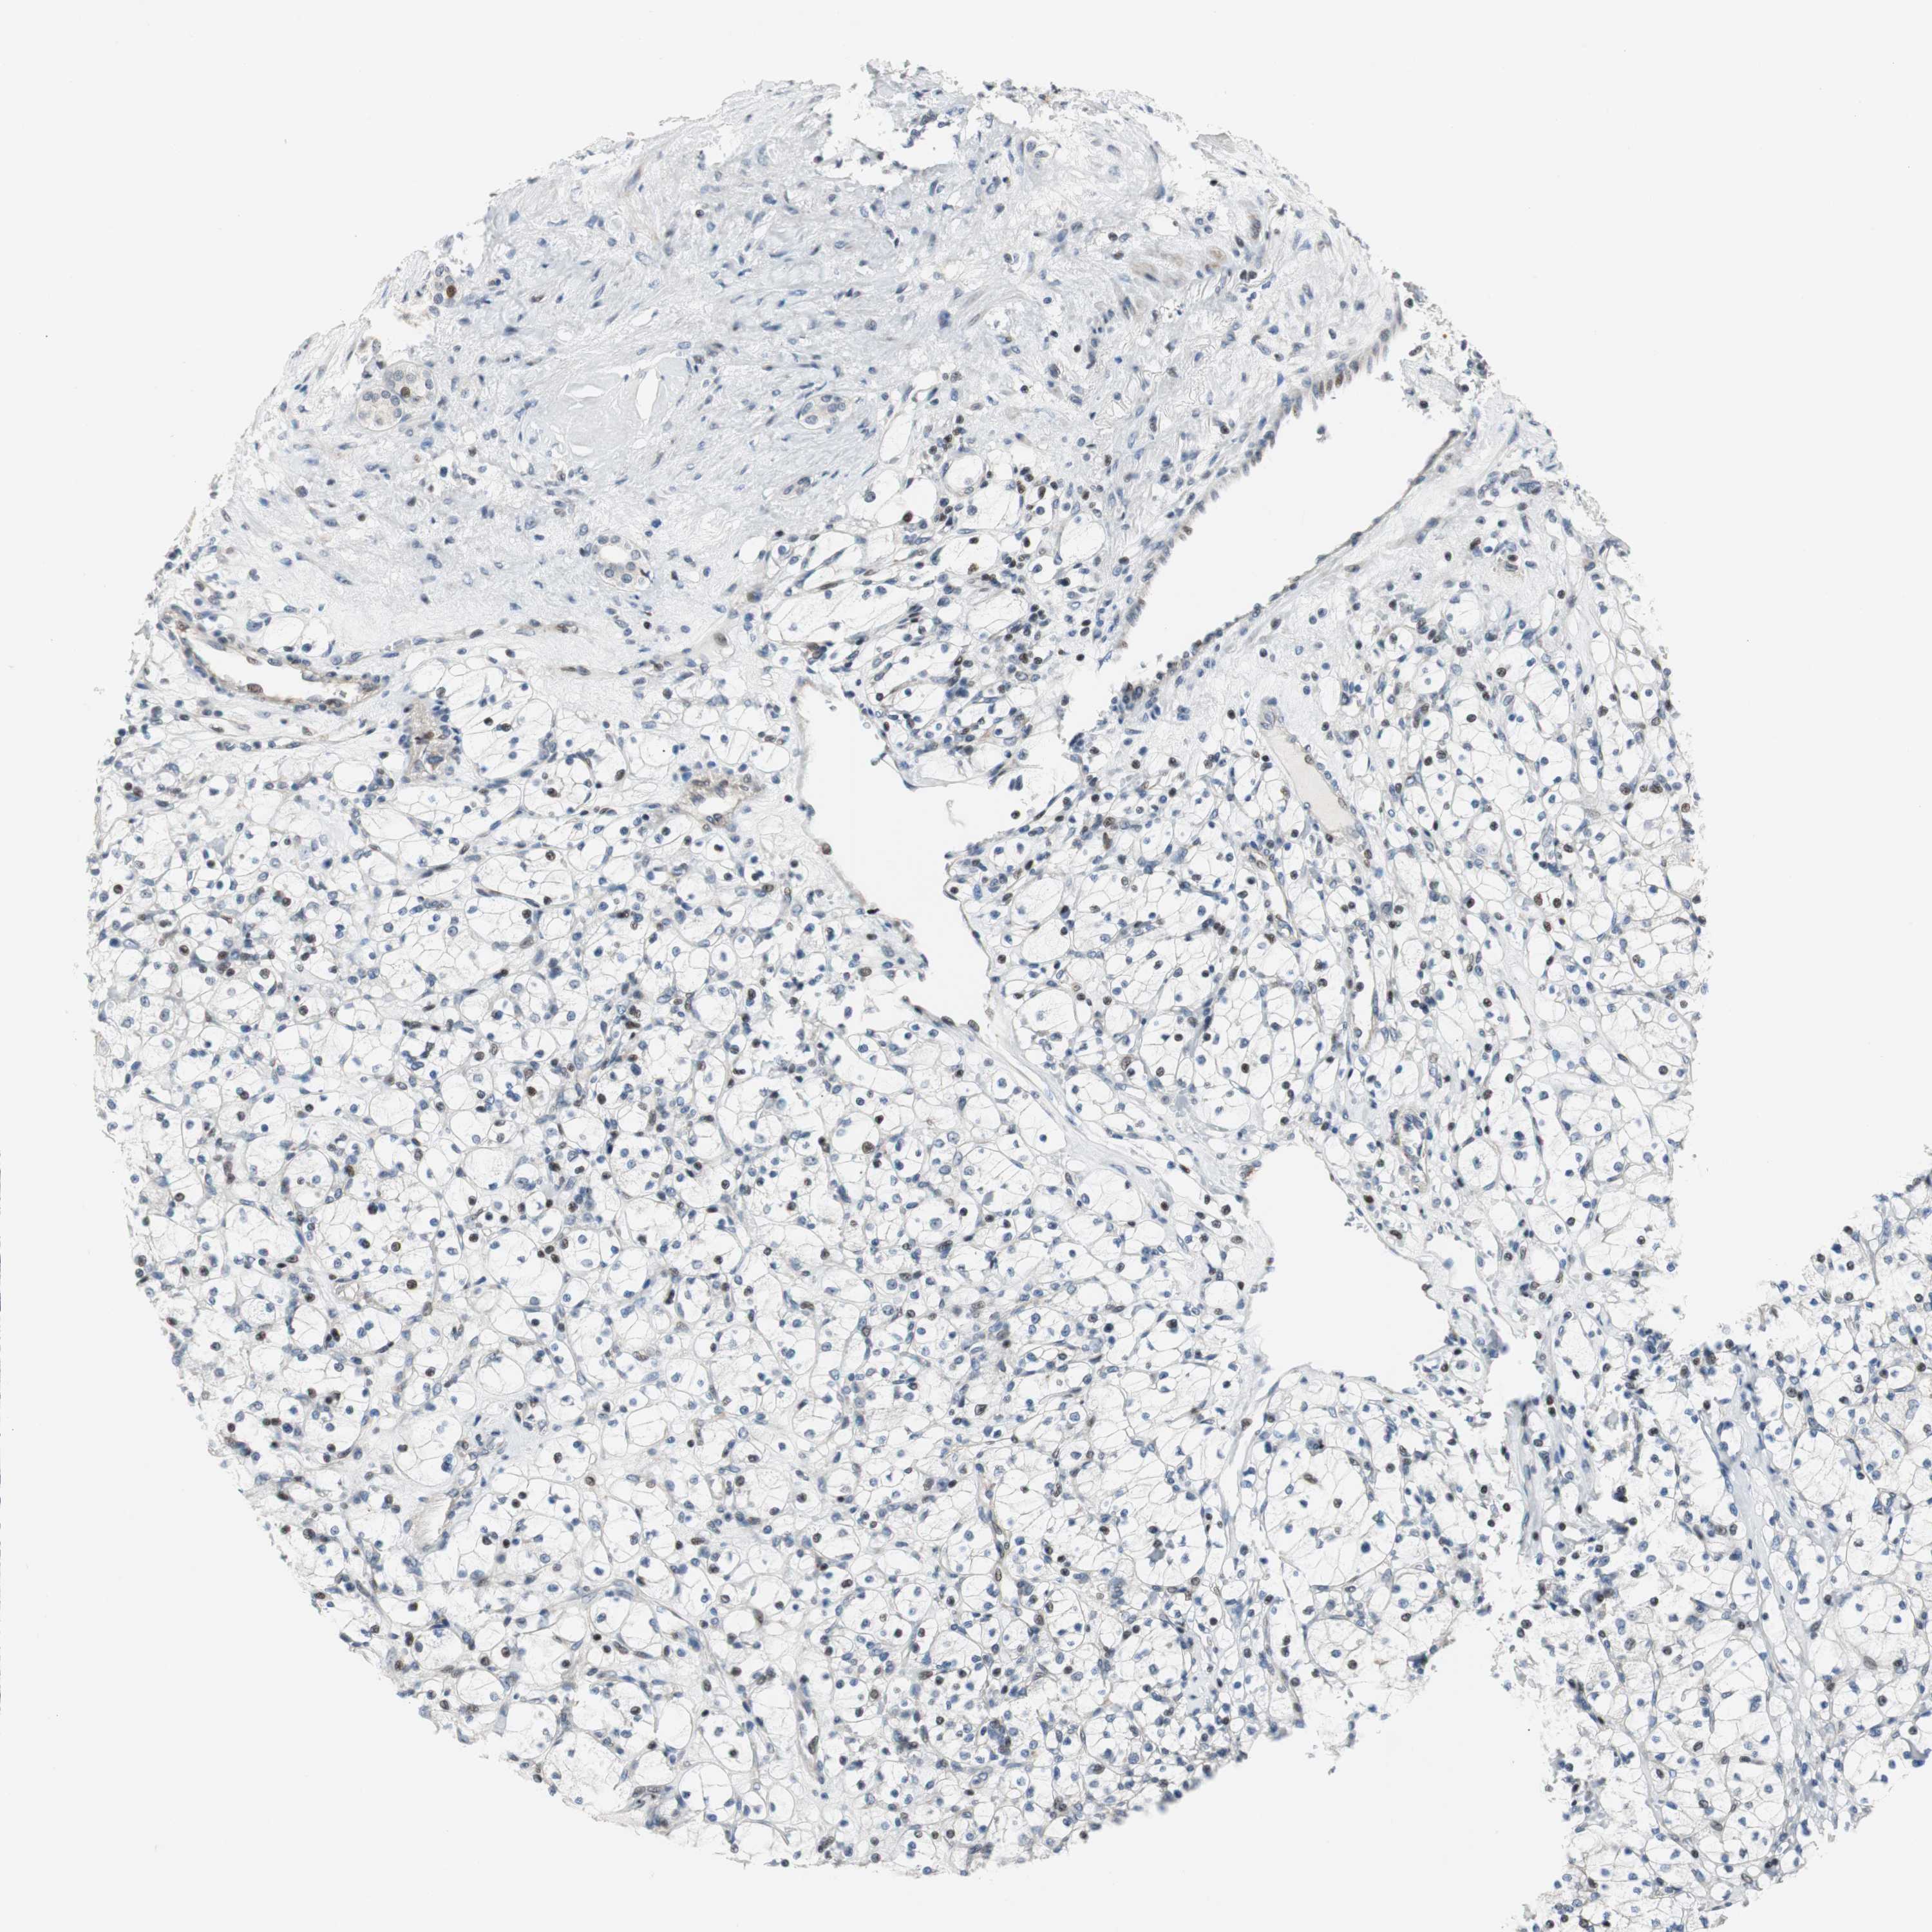

KIDNEY RENAL CLEAR CELL CARCINOMA (VALIDATION) - Interactive survival scatter ploti

The Survival Scatter plot shows the clinical status (i.e. dead or alive) for all individuals in the patient cohort, based on the same data that underlies the corresponding Kaplan-Meier plots. Patients that are alive at last time for follow-up are shown in blue and patients who have died during the study are shown in red.

The x-axis shows the expression levels (FPKM) of the investigated gene in the tumor tissue at the time of diagnosis. The y-axis shows the follow-up time after diagnosis (years). Both axes are complimented with kernel density curves demonstrating the data density over the axes. The top density plot shows the expression levels (FPKM) distribution among dead (red) and alive patients (blue). The right density plot shows the data density of the survived years of dead patients with high and low expression levels respectively, stratified using the cutoff indicated by the vertical dashed line through the Survival Scatter plot. This cutoff is automatically defined based on the FPKM cutoff that minimizes the p-score. The cutoff can be changed by dragging the vertical line or by entering a cutoff value in the square labeled "Current cut-off".

Under the Survival Scatter plot the p-score landscape (black curve; left axis) is shown together with dead median separation (red curve; right axis). Dead median separation is the difference in median mRNA expression between patients who have died with high and low expression, respectively. It is calculated as follows: median FPKM expression of dead patients with high expression - median FPKM expression of dead patients with low expression. This is intended to aid the user in visually exploring custom cutoffs and the associated p-scores and dead median separation.

Individual patient data is displayed and can be filtered by clicking on one or more of the category buttons on the top of the page. Categories describing expression level and patient information include: high, low, alive, dead, female, male and tumor stages. The scale of the x-axis can be toggled between linear and log-scale by clicking on the "x log" button. Mouse-over function shows TCGA ID, patient information and mRNA expression (FPKM) for each patient.

& Survival analysisi

Kaplan-Meier plots summarize results from analysis of correlation between mRNA expression level and patient survival. Patients were divided based on level of expression into one of the two groups "low" (under cut off) or "high" (over cut off). X-axis shows time for survival (years) and y-axis shows the probability of survival, where 1.0 corresponds to 100 percent.

RAD1 is not prognostic in Kidney Renal Clear Cell Carcinoma (validation)

TCGA RNA samplesi

RNA-seq data is reported as average FPKM (number Fragments Per Kilobase of exon per Million reads), generated by the The Cancer Genome Atlas (TCGA) .

Normal distribution across the dataset is visualized with box plots, shown as median and 25th and 75th percentiles. Points are displayed as outliers if they are above or below 1.5 times the interquartile range. FPKM values of the individual samples are presented next to the box plot.

Average pTPM 6.6

Number of samples 100